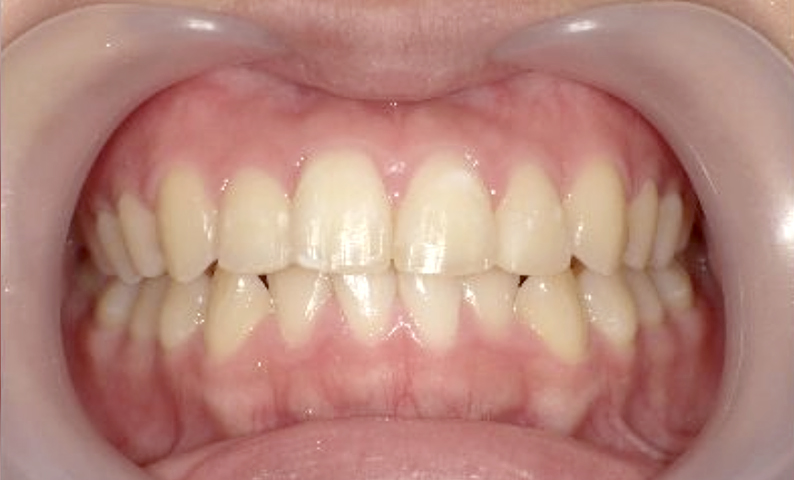

症例_001 上下顎の部分矯正

治療期間:12ヶ月金額:54万円+税女性前歯のガタガタ逆八の字

| Before | After |